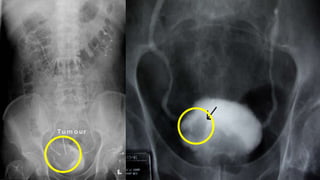

IMAGING STUDIES….. EAU

TRANSABDOMINAL

ULTRASOUND….. ADVANTAGES

• Characterisation of Renal masses

• Detection of hydronephrosis

• Visualisation of intraluminal masses in the bladder.

Ultrasound is therefore a useful tool for detection of

obstruction in patients with haematuria.

ULTRASOUND….. LIMITATIONS

•Cannot exclude the presence of Upper Tract

Urothelial Carcinoma and therefore, cannot replace

CT urography.

•The diagnosis of CIS cannot be made with

Ultrasound.

IMAGING STUDIES….. EAU TRANSABDOMINAL ULTRASOUND…..ADVANTAGES • Characterisation of Renal masses • Detection of hydronephrosis • Visualisation of intraluminal masses in the bladder. Ultrasound is therefore a useful tool for detection of obstruction in patients with haematuria.

IMAGING STUDIES….. EAU TRANSABDOMINAL ULTRASOUND…..LIMITATIONS •Cannot exclude the presence of Upper Tract Urothelial Carcinoma and therefore, cannot replace CT urography. •The diagnosis of CIS cannot be made with Ultrasound.